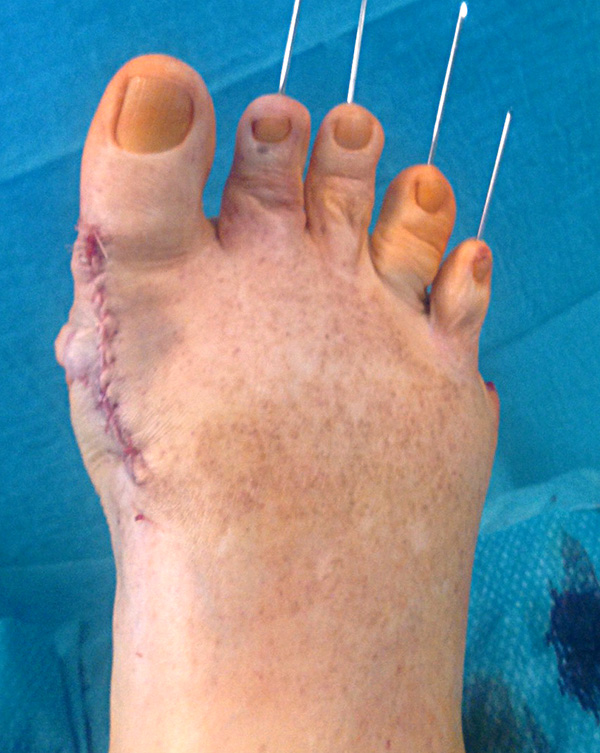

Abschließend erfolgt die temporäre K-Daht Fixation sämtlicher Kleinzehen in achsgerechter Stellung. Die Strecksehnen werden in Verlängerung vernäht.

Mobilisation des Patienten im flachen Verband-Schuh für 4-6 Wochen. Die Dauer richtet sich nach der Therapie im Bereich des ersten Strahls.

Anleitung des Patienten in der Pflege der K-Drähte, Verbandswechsel und gegebenenfalls Zehen zügeln.

Der Fadenzug erfolgt plantar nach 21 Tagen. Fäden am Fußrücken können nach 14 Tagen entfernt werden.

Die Entfernung der K-Drähte wird sechs Wochen postoperativ im Rahmen der Sprechstunde geplant. Anschließend empfiehlt sich eine weitere Redression der Kleinzehen bis 3 Monate postoperativ bis sich das Narbengewebe ausreichend stabilisiert hat.